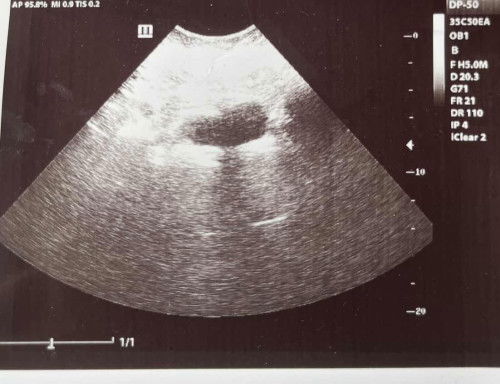

Ad nampak apa ii tak

Sy nk tanya korang ad nampak apa apa ke

Lmp ; 2 november 2024

Mumy 6wk 5day